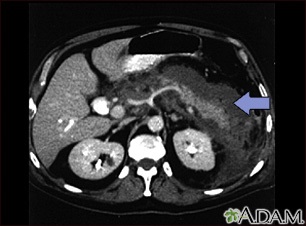

The following imaging tests that can show swelling of the pancreas may be done, but are not always needed to make a diagnosis of acute pancreatitis: